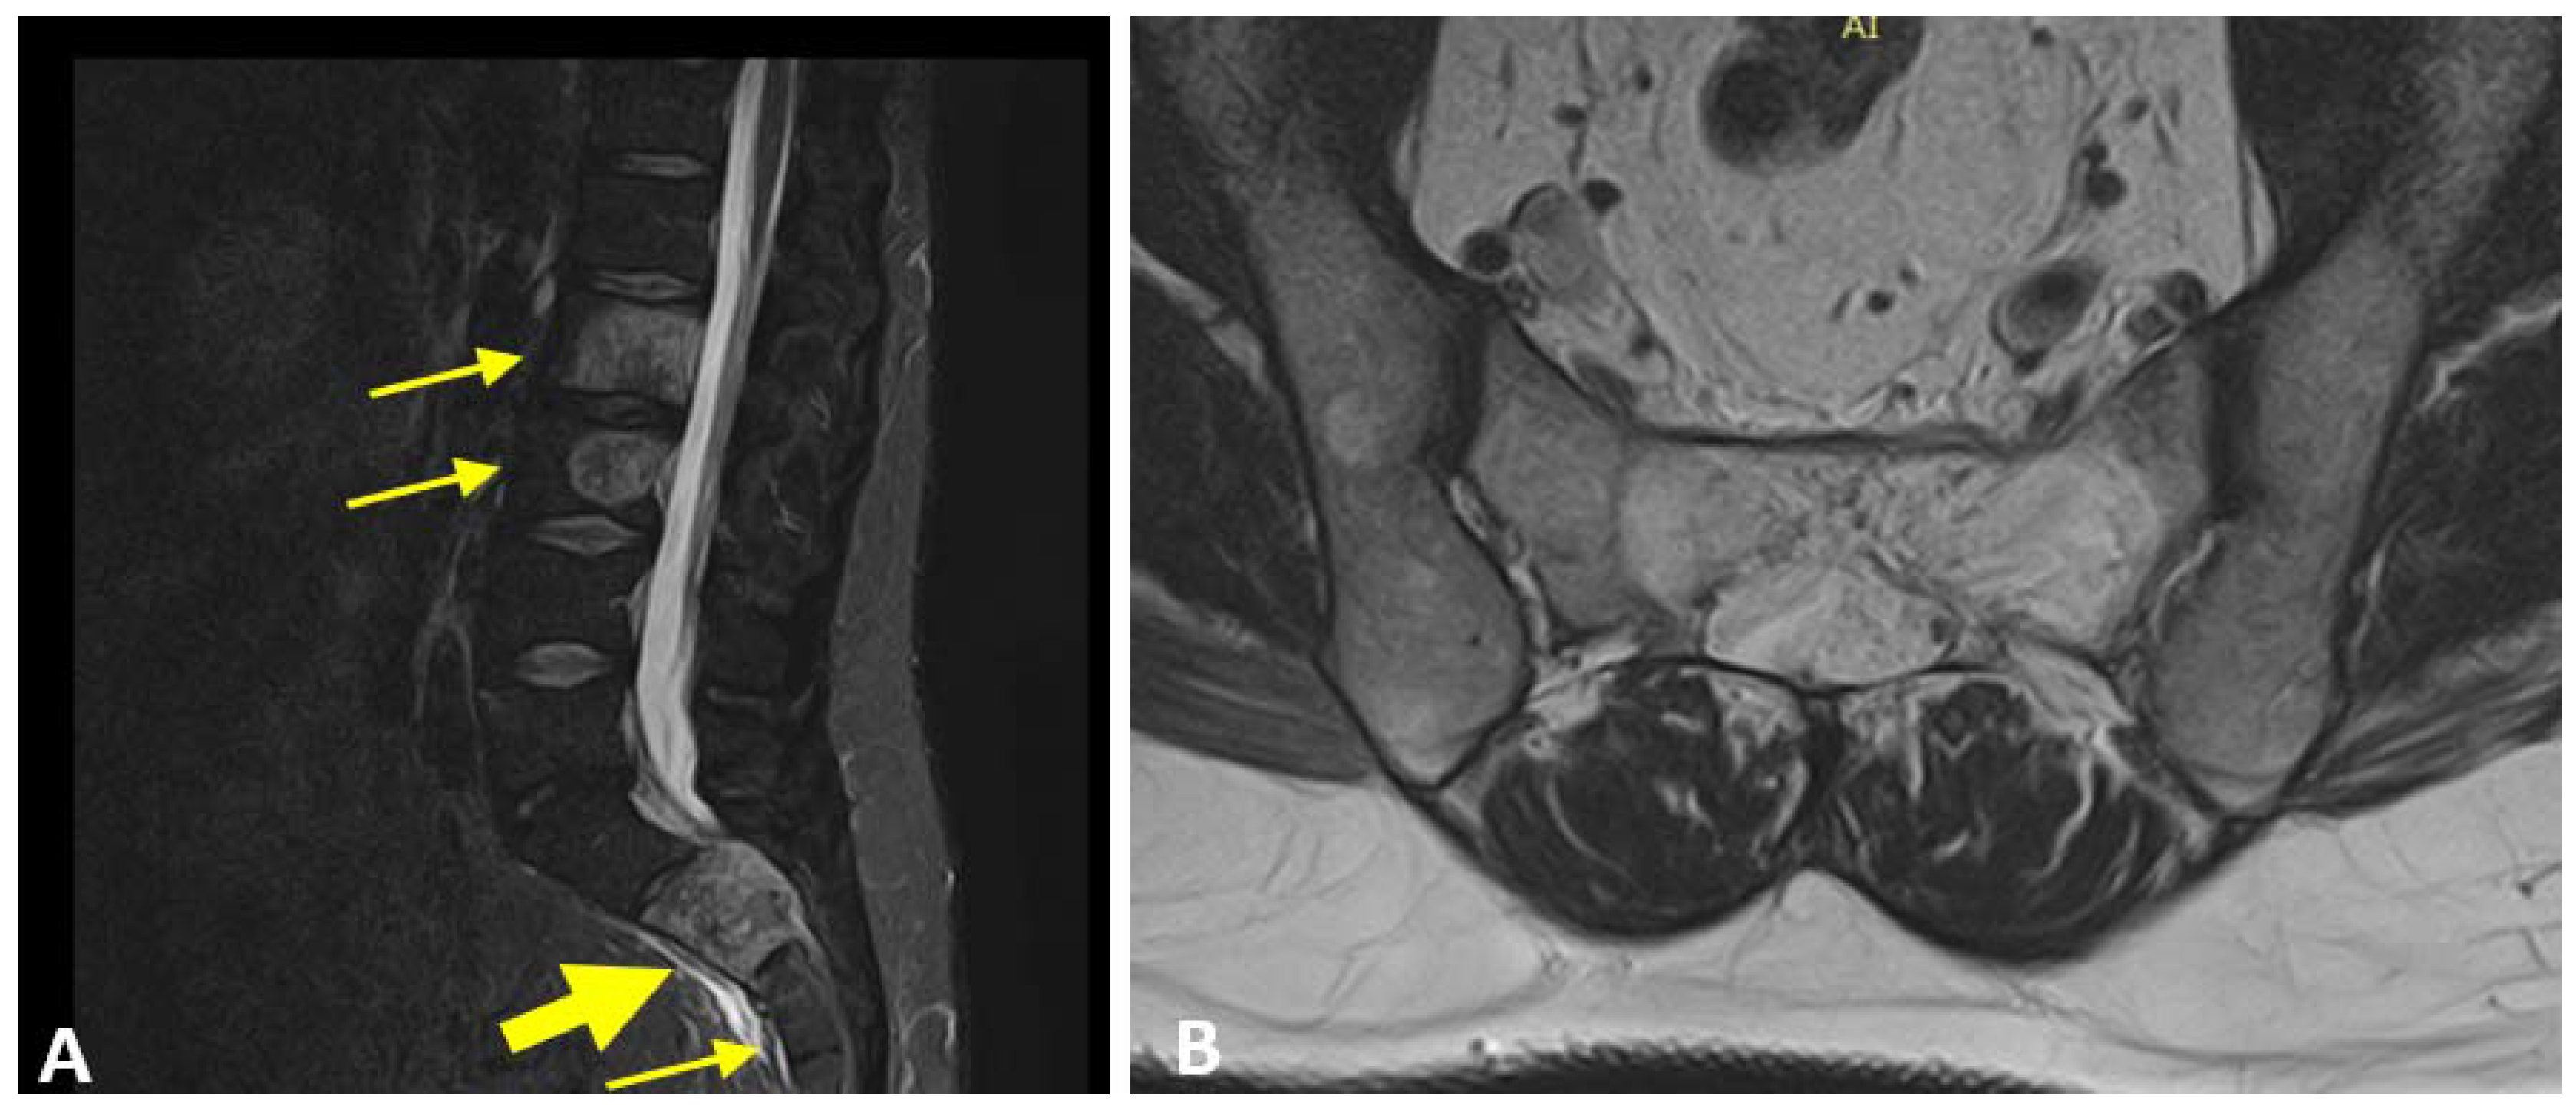

Aggressive Vertebral Hemangioma and Spinal Cord Compression: A Particular Direct Access Case of Low Back Pain to Be Managed—A Case Report

2. Case Description